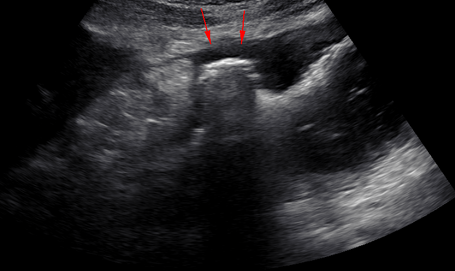

胃潰瘍とは、胃の粘膜に炎症が起きて、深い傷(潰瘍)ができている状態を指します。

• 超音波検査